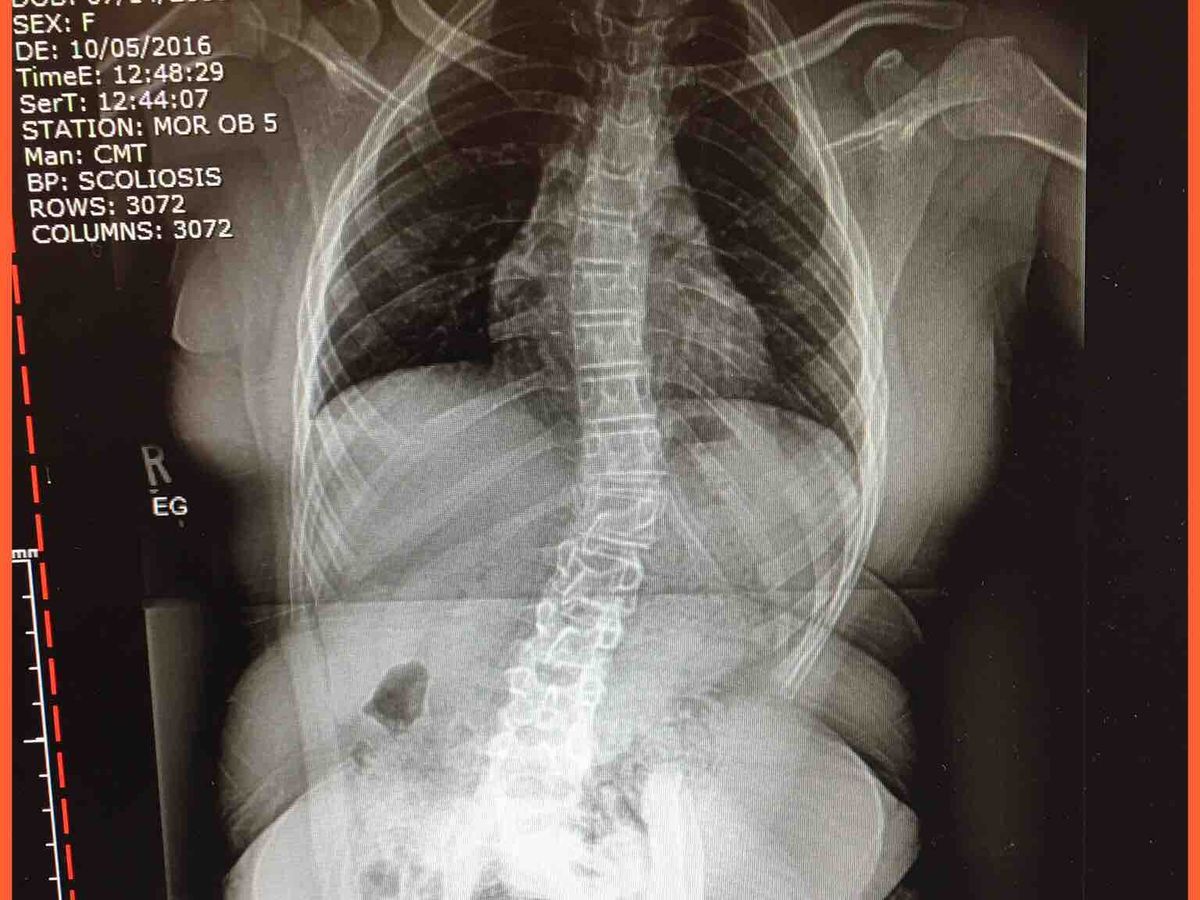

The  Warrior Princess is at it again.  She has been recovering from a broken femur for close to two years. During that time she had numerous surgeries and was diagnosed with severe scoliosis.  Not only does she have a lumbar curve she also has a thoracic curve.  We moved to Florida and it has taken 9 months to find a surgeon who would take her as their patient. I had taken her to 5 surgeons who all insisted that I go back home to the doctor who knew her the best. They were all afraid of causing her more problems and not being able to properly care for her. They wouldn't even release her for therapy.  After a conversation with her surgeon back home she suggested that I take Isabella to Miami to the Orthopedic Trauma Center. A few weeks ago I made the trip with her and met with Dr. Schoenleber and while consulting with him he called his colleague Dr. George to look at the xrays for Isabella's spine.  He called her scoliosis  "progressive" and changing quickly.  Her lower spine was at a 50% and thoracic at 45%, a 20% increase since February when she saw a scoliosis specialist closer to home.  He discussed a plan with me and Dr. Schoenleber agreed that before addressing her hips and leg (still healing from the break 2 years ago), that her back must be fixed. Isabella was scheduled for Scoliosis surgery on July 20th,  a week after her 12th birthday.  This will be a completely new surgery for her with new doctors.  Her hospital stay shouldn't be long but it really depends on how she does.  She will have bi weekly follow ups at first and then monthly.  She is expected to be back to 100% with in 6 months and Dr. Schoenleber will see her again at the 3 months mark to put a plan together for him surgery and hardware removal and replacement.